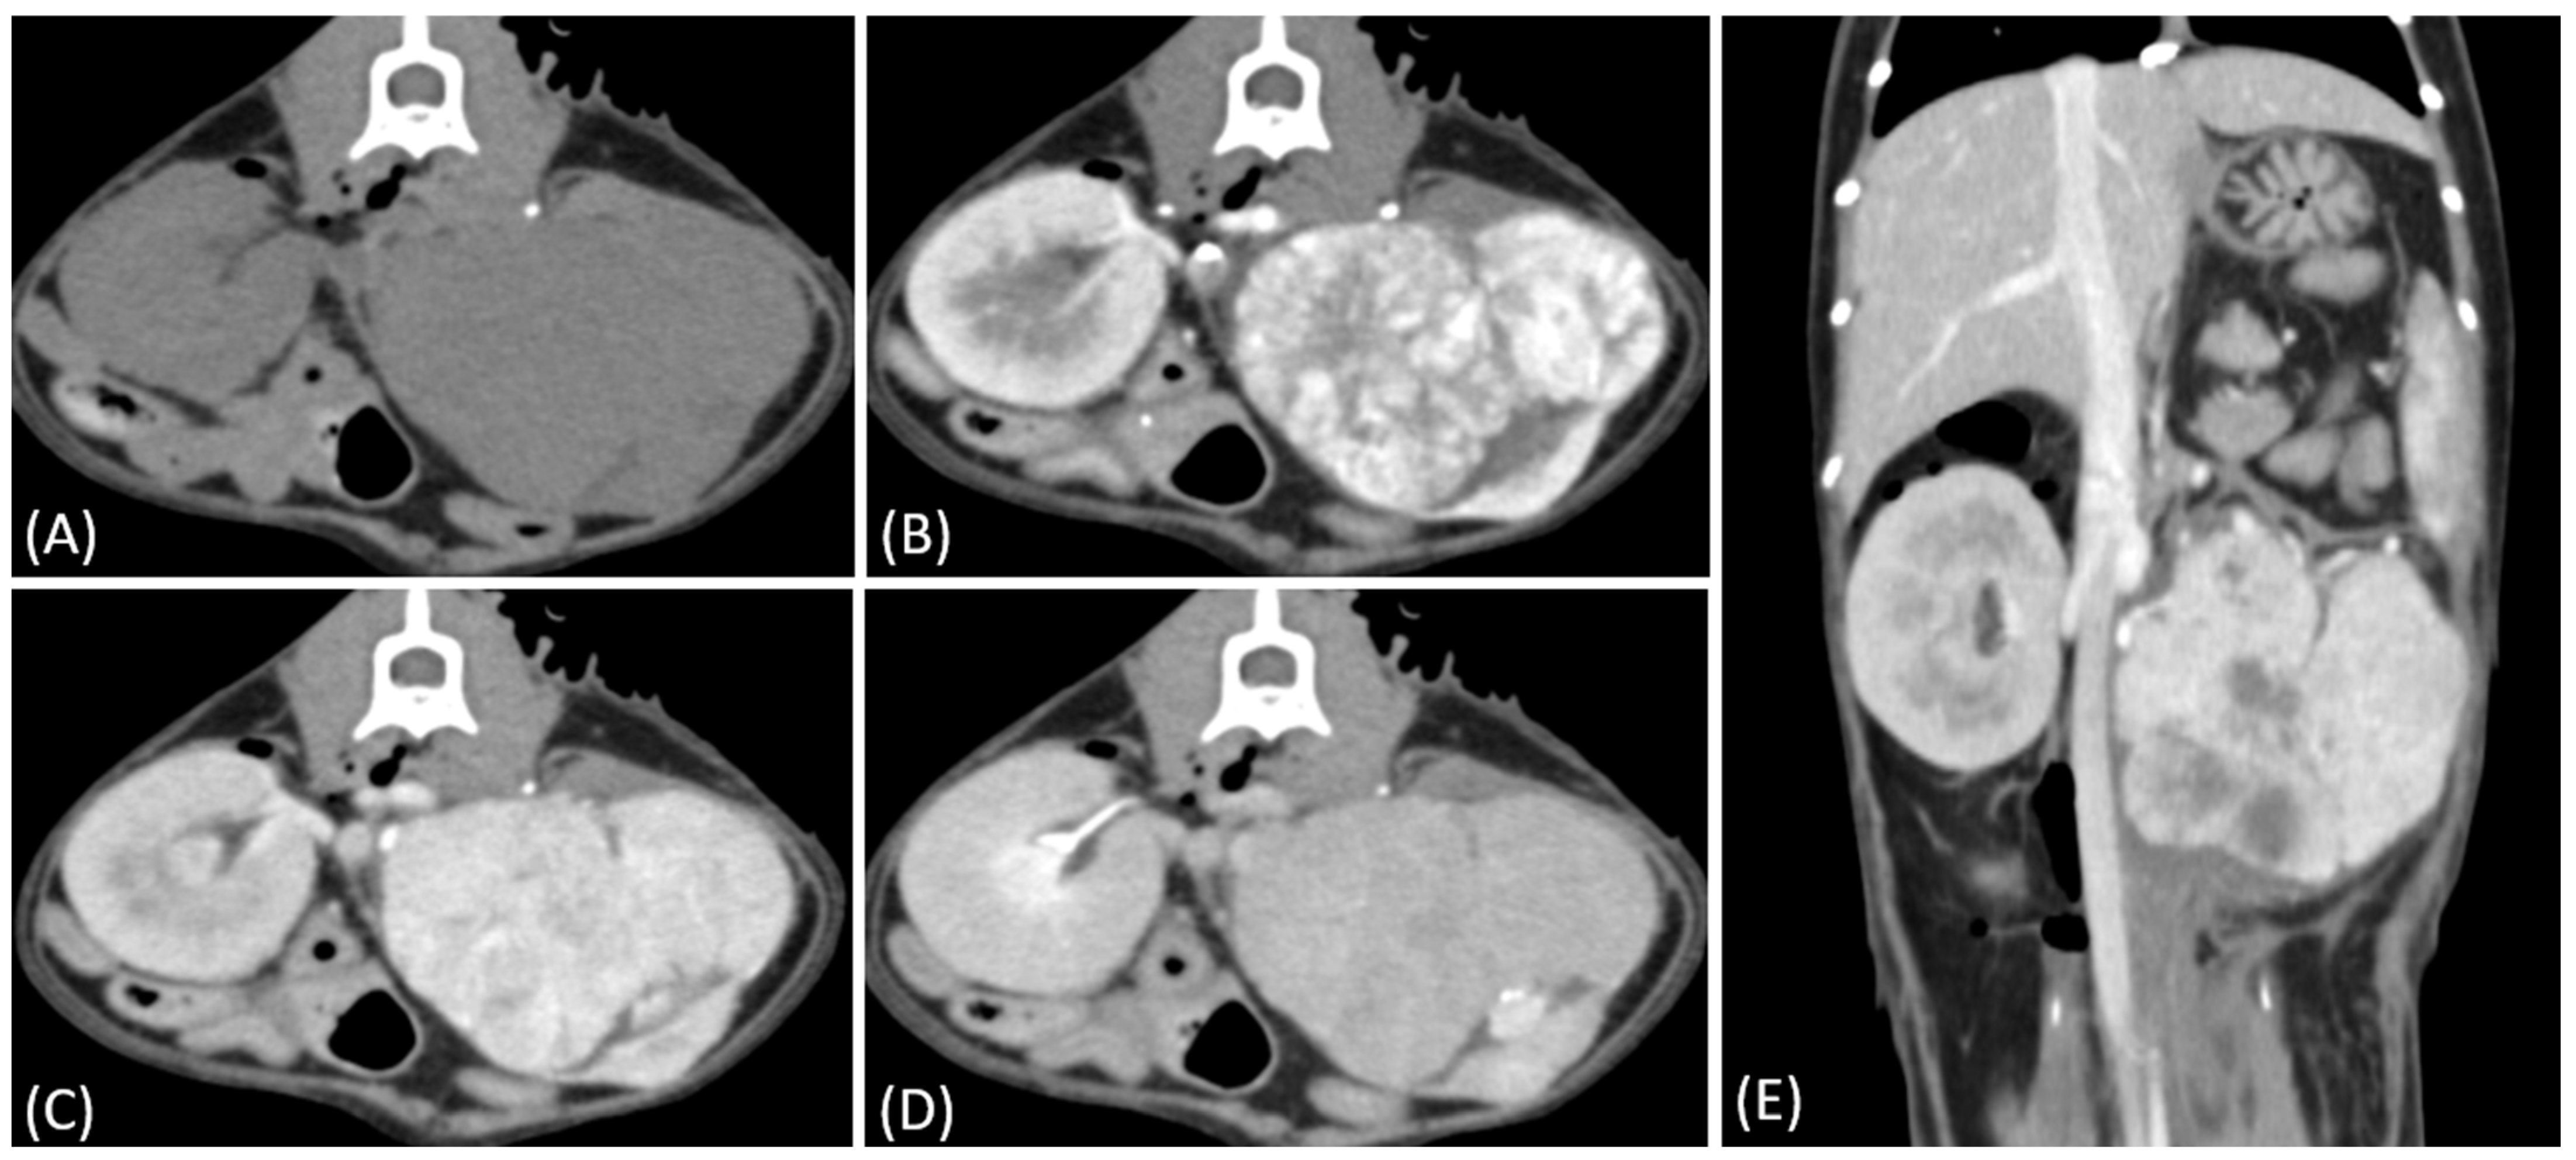

Figure 3.

(A) Pre-contrast, (B) corticomedullary phase, (C) nephrographic phase, and (D) delayed nephrographic/early excretory phase contrast-enhanced computed tomography (CT) images of a cat with bilateral renal and small intestinal lymphoma. The right kidney shows an infiltrative mass (black arrow), while the left kidney has an expansile mass (white arrow). Both tumors are homogeneous and hypodense, demonstrating progressive enhancement.

Figure 4.

(A) Pre-contrast, (B) corticomedullary phase, (C) nephrographic phase, and (D) delayed nephrographic/early excretory phase contrast-enhanced computed tomography (CT) images of a renal cell carcinoma. The tumors are bilateral, predominantly demonstrating an expansile growth pattern. They appear relatively homogeneous and hypoattenuating, resembling the imaging characteristics of multiple lymphoma masses. Progressive enhancement is observed throughout the phases. These findings highlight the overlapping imaging features between renal cell carcinoma (RCC) and lymphoma in certain cases.